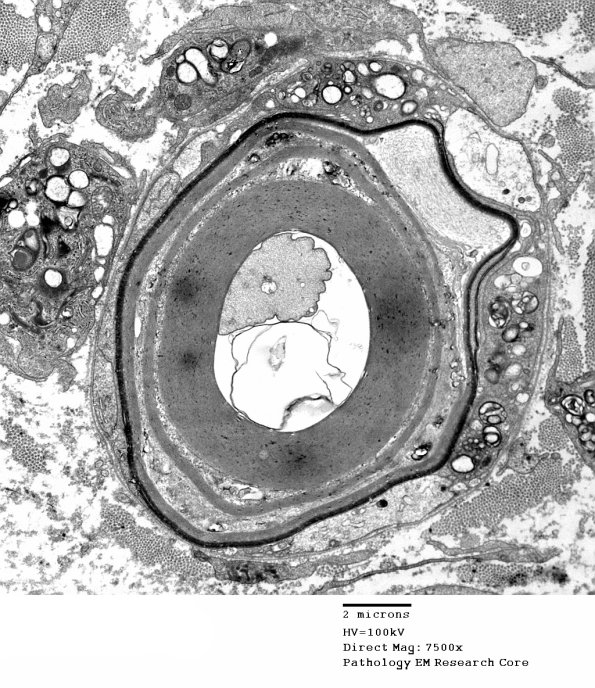

1D9A-D The shape and layers of peeled myelin and multiple macrophages gathered around this axon appears complex.